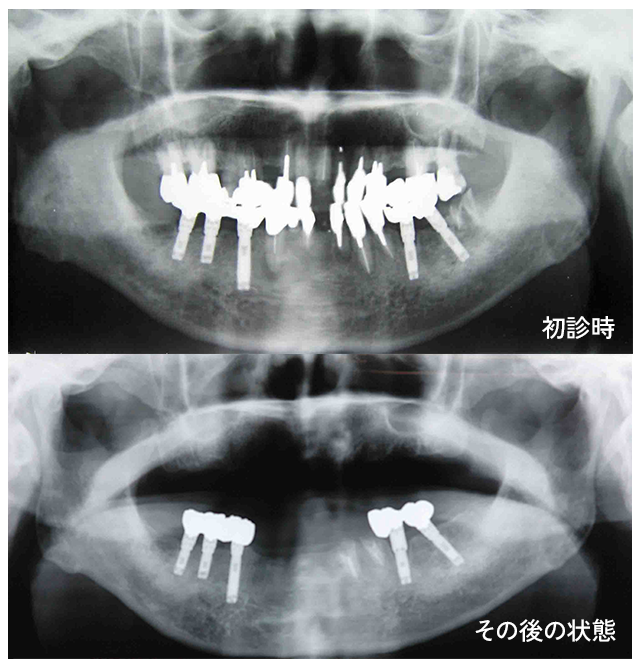

井上先生は東京歯科大学を卒業した後に大学の補綴科で10年間インプラントと義歯を学びました。

そのまま補綴を極める道を歩んでいこうとしていたようなのですが、インプラント治療終了後に10年も経たないでインプラント以外の歯が全部なくなった患者さんを目の当たりにして補綴治療領域の限界を感じ、そもそも補綴を必要としないための予防へと専攻を変えました。